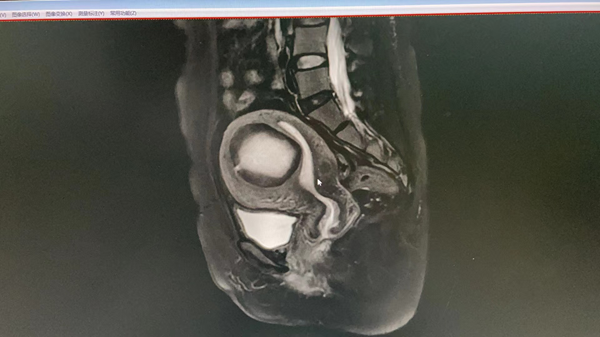

社区B超示:子宫前壁一大小约6.8cm*6cm*6cm低回声团,紧邻内膜,考虑子宫肌瘤。门诊查白带、HPV、TCT结果未见异常。入院后完善各项检查,盆腔MRI提示:子宫前壁一大小约6.8cm*6cm*5.5cm肌瘤。肝、胆、脾、胰、泌尿系彩超、血常规、血脂、肝肾功能、生化、凝血、心电图、胸片等结果均未见明显异常。

MRI图片